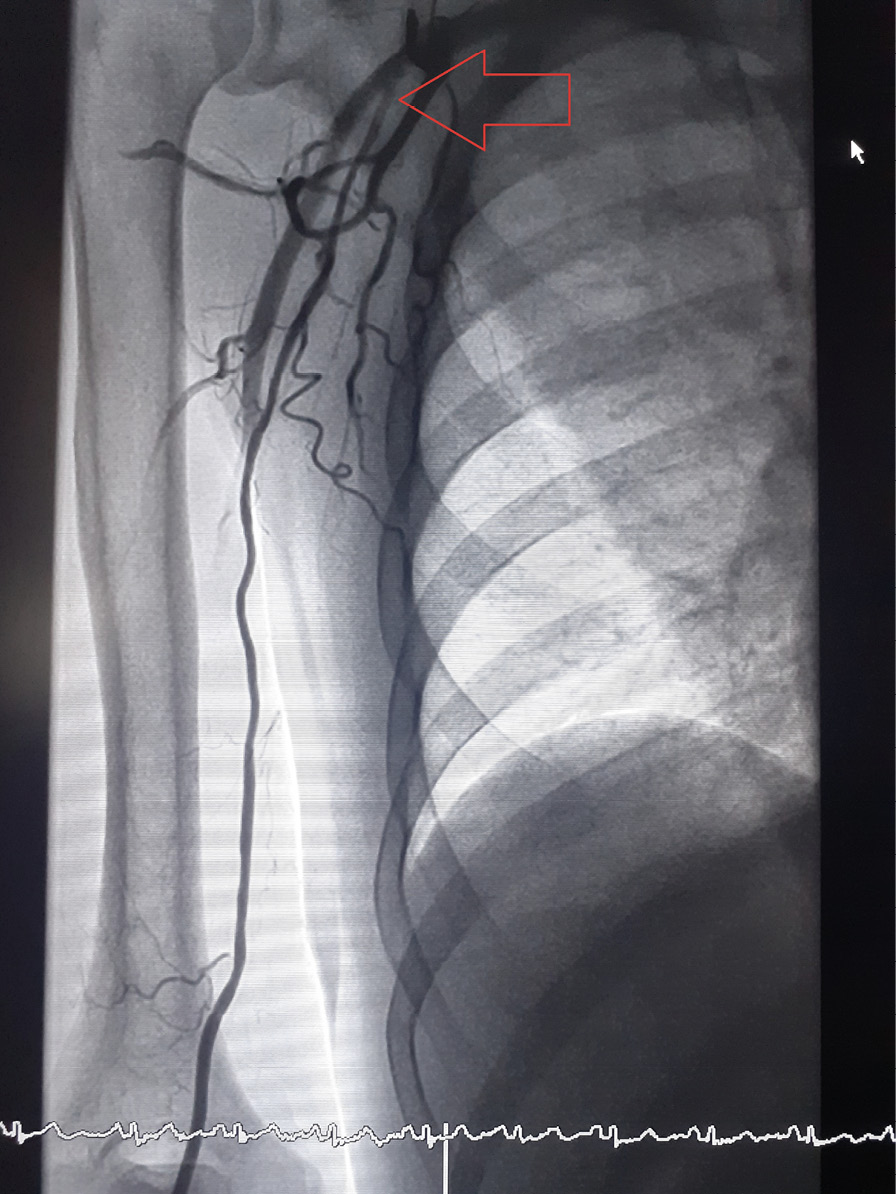

Рис. 2. Дорсопальмарный (модифицированный дистальный) лучевой доступ: контрольная ангиография доступа (красной стрелкой указана область пункции лучевой артерии, зеленой стрелкой – поверхностная ладонная ветвь лучевой артерии r. superficialis)

Статистически значимых различий в показателях количества попыток, продолжительности пункции лучевой артерии, времени процедуры, флюороскопии, конверсии у пациентов групп ТРД и ДпЛД выявлено не было (табл. 2). Все 6 случаев конверсии были обусловлены спазмом на этапе пункции или заведения проводника. У 5 пациентов группы ДпЛД был налажен ТРД через лучевую артерию предплечья ипсилатеральной верхней конечности. У 1 пациента группы ТРД для конверсии использовалась лучевая артерия предплечья контралатеральной руки. Конверсий на феморальный доступ не было. Случаев спазма лучевой артерии в процессе процедуры, потребовавшего отказа от доступа, не отмечалось. У 5 пациентов (1 (1%) из группы ТРД и 4 (4%) из группы ДпЛД) наблюдалась аномалия развития: высокое отхождение лучевой артерии (рис. 3), не оказавшее существенного влияния на общую продолжительность процедуры, однако потребовавшее дополнительного введения РКВ для его верификации, тем самым оказав влияние на разницу показателей расхода РКВ в группах ТРД и ДпЛД (195 (150; 400) мл в группе ТРД и 214 (150; 350) мл в группе ДпЛД, p = 0,005). Контрольная артериография лучевой артерии, выполненная после ЧКВ, не выявила случаев перфорации и значимых диссекций. Оценка субъективного комфорта процедуры гемостаза по вербальной описательной шкале оценки боли Gaston-Johansson выявила статистически значимое преимущество ДпЛД перед ТРД (6,4 (4; 10) в группе ТРД и 1,7 (0; 6) в группе ДпЛД, p < 0,001). Частота возникновения гематом 3-й степени по шкале EASY была статистически значимо выше в группе ТРД, отмечено пятикратное превышение данного показателя по сравнению с группой ДпЛД (15 (15%) пациентов в группе ТРД против 3 (3%) пациентов в группе ДпЛД, р = 0,004) (табл. 3). Гематом 4-й степени по шкале EASY в группе ДпЛД выявлено не было, тогда как в группе ТРД они возникли в 4 (4%) случаях. Гематомы 5-й степени по шкале EASY не регистрировались ни в одной из групп.

Рис. 3. Аберрантная лучевая артерия, отходящая от подмышечной артерии (уровень отхождения указан красной стрелкой)